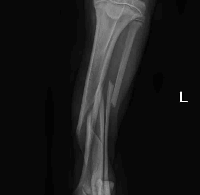

Após exames recebemos a seguinte notícia:

Em relação às fraturas, além da perninha esquerda, ela tem também fraturas em pelve. O ortopedista nos repassou o orçamento de R$2950,00 para o procedimento cirúrgico (incluindo o valor da anestesia e uma diária de pós operatório). Na ultrassonografia abdominal, foi identificado apenas sinais de gastrite. Os exames de sangue devem ser liberados agora pela manhã ainda.